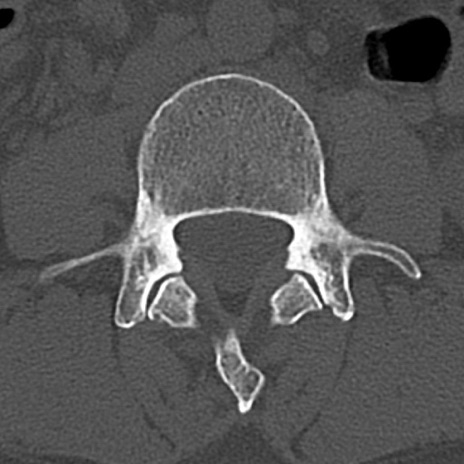

腰椎CT

横断像と矢状断像